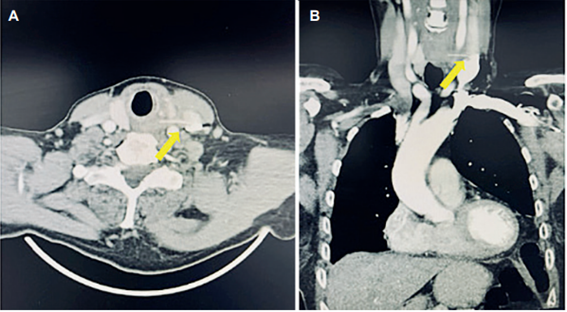

Referente al manejo (Tabla 2), 15 (68,2 %) pacientes fueron tratados de forma conservadora y en 7 pacientes (31,8 %) se hizo cirugía. Todos los pacientes recibieron antibioticoterapia desde el momento de la consulta, y en ninguno se evidenció una infección asociada a la perforación durante todo el tratamiento. Por endoscopia, los cuerpos extraños fueron identificados y extraídos en 8 (36,4 %) casos. Destacamos el caso de un paciente con migración de una espina de pescado desde la faringe, penetrando la vena yugular interna izquierda, que recibió manejo quirúrgico (Figura 1). Previo al egreso se realizó esofagograma de control en 15 pacientes (68,2 %) y en ninguno de ellos se evidenció fuga del medio de contraste; los demás pacientes recibieron alimentos directamente y de igual manera, no se registraron fugas.

Los cuerpos extraños pueden causar perforación por punción directa, lesión química, compresión/isquemia o desgarro al extraerlo 7,11,16,17. Representan entre el 7 % y el 14 % de las perforaciones esofágicas y generalmente se localizan a nivel de las tres estrecheces esofágicas anatómicas, con mayor frecuencia en la unión cricofaríngea 4,11. También se puede presentar migración de los cuerpos extraños, llegando a alojarse en espacios vasculares, como observamos en el paciente de la Figura 1.